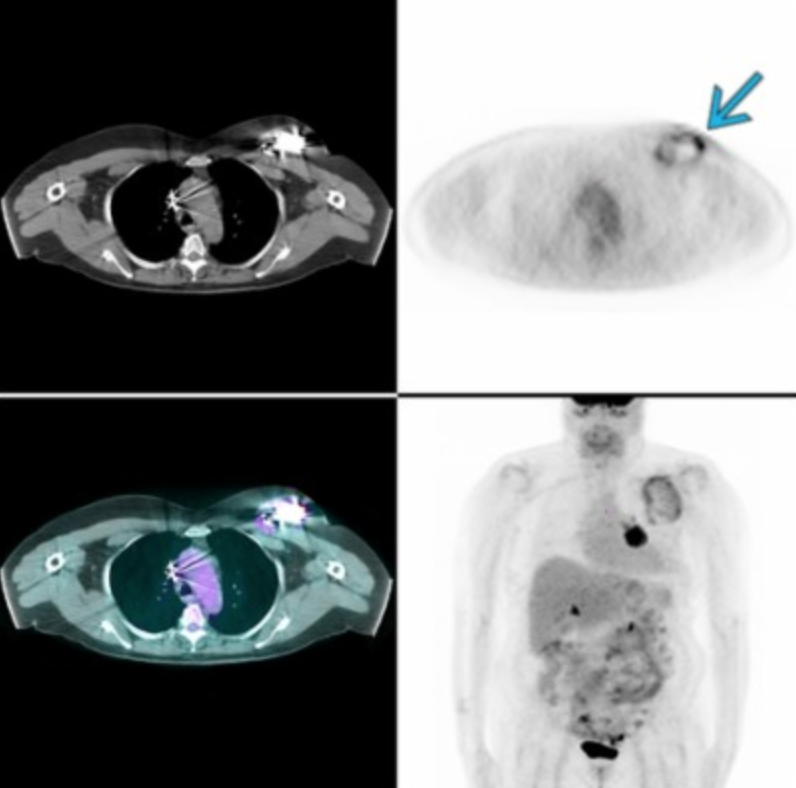

Infected ICD

Brown Fat

• Mostly seen in the neck, cervicothoracic paraspinal soft tissues, clavicular region and mediastinum

• Can also see in peri-renal area (looks like adrenal gland but obv is not the adrenal gland)

• When determining if brown fat or abnormal look for

• Symmetry

• Look for no lesions and just fat on the regular non-con CT

• Look for no surrounding abnormal LN

• How to reduce this

• Keep room warm

• Give benzodiazepines - shuts down pathway